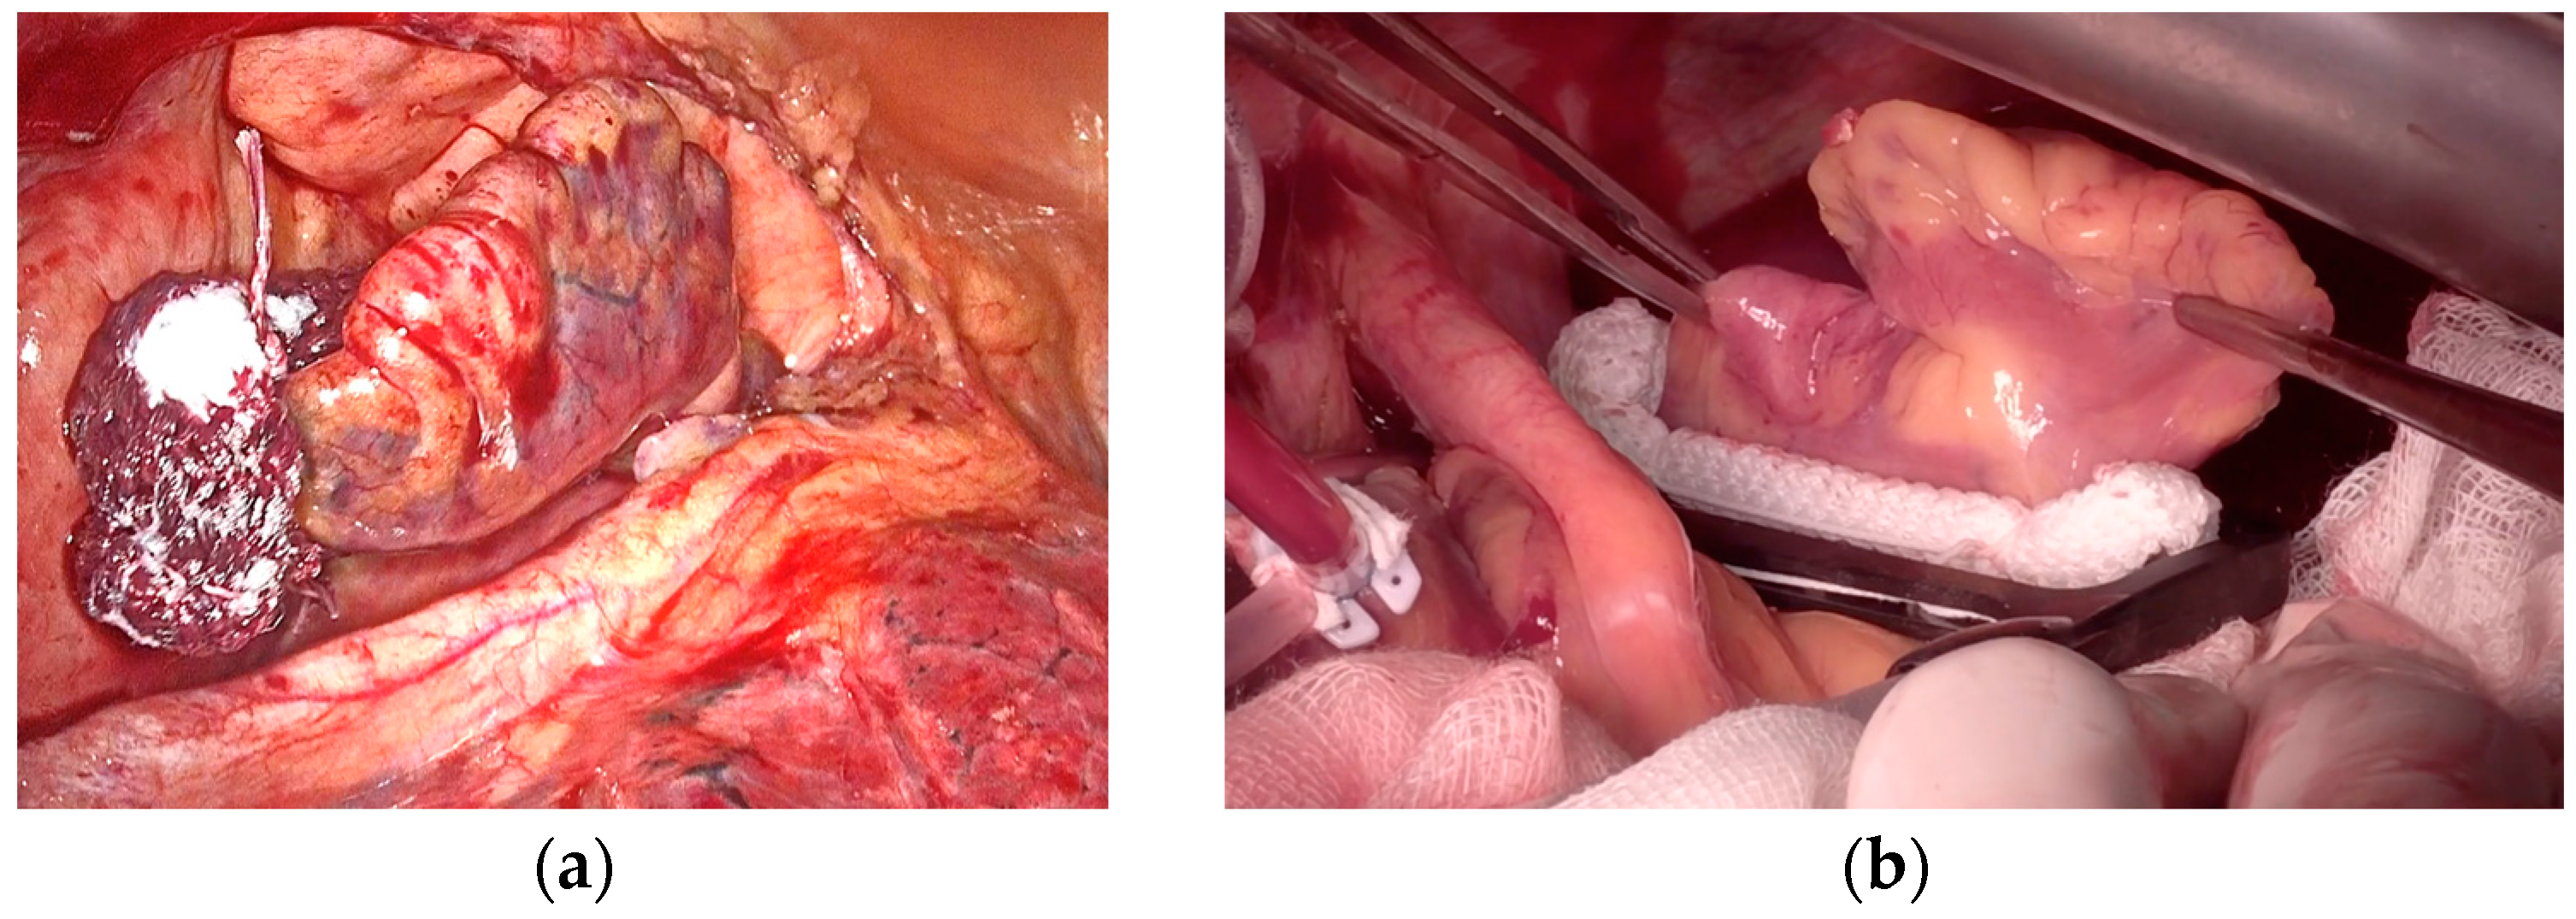

- Lee, R.; Vassallo, P.; Kruse, J.; Malaisrie, S.C.; Rigolin, V.; Andrei, A.C.; McCarthy, P. A Randomized, Prospective Pilot Comparison of 3 Atrial Appendage Elimination Techniques: Internal Ligation, Stapled Excision, and Surgical Excision. J. Thorac. Cardiovasc. Surg. 2016, 152, 1075–1080. [Google Scholar] [CrossRef]